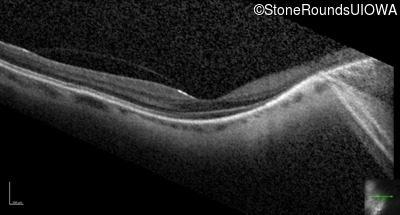

Optical Coherence Tomography - Left - 20/25 -2

Exemplar / OCT Stack

OCT Stack